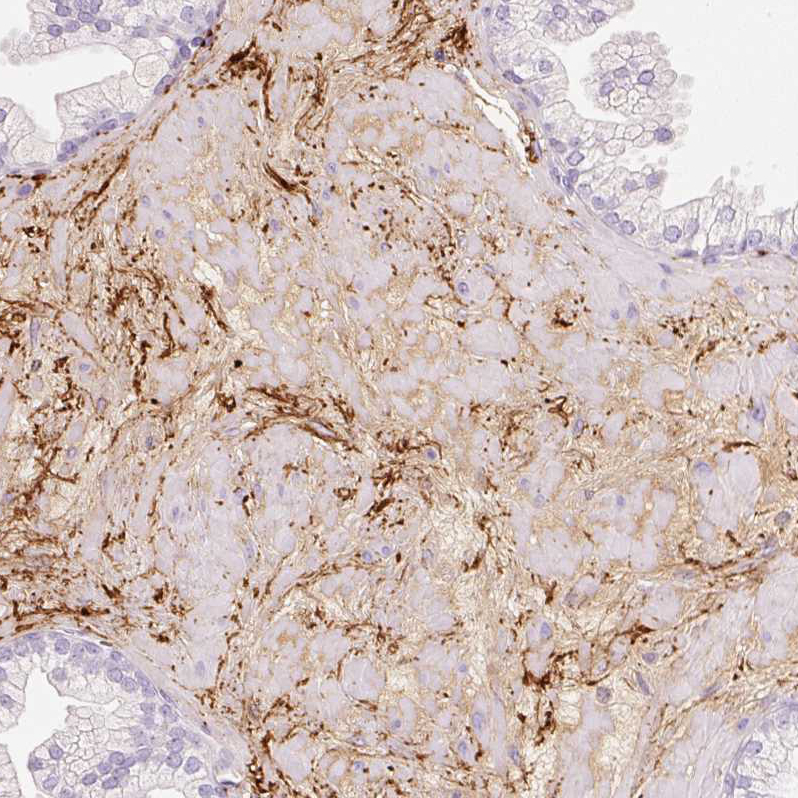

Immunohistochemical staining of human lung shows moderate extracellular space positivity in pneumocytes and macrophages.